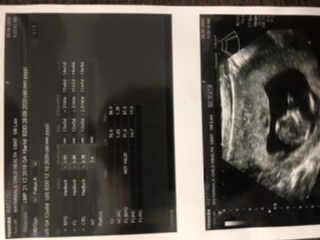

I am expecting my 3rd child with normal delivery. According to my LMP my EDD is suppose to be 26/9/2020 but in scan its showing 12/10/2020. In this pregnancy i have had on and off spotting and sharp uterus pains. I have low hemoglobin level. I am constantly feeling sick constant headaches, really fatigue unable to do daily chores inconsistency in passing urine and severe constipation. Please guide how to deal with these issues. I have been constantly taking paracetamol and loratadine for itching.

Kindly share your last menstrual period date.. This scan is not clearly visible to me so please mention the gestational age given by this scan and the date on which it was done.

The last monthly period was on 21/12/2019.

Due date by the scan is 12/10/2020.

Scan was done on 5/4/2020